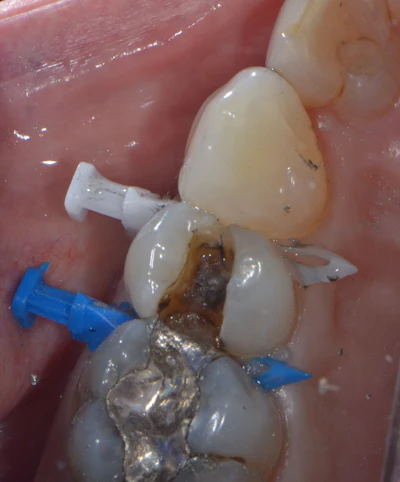

Figure 3: Upper premolar with failing disto-occlusal amalgam restoration.

Figure 4: Upper premolar with amalgam removal completed under Isolite (Zyris) isolation. Crack on the mesial is visualized.

In this clinical case, a large failing amalgam was removed from an upper premolar during an emergency visit (Figures 3, 4, 5). The initial pulpal diagnosis was reversible pulpitis. Due to the large crack on the mesial, a composite buildup was placed initially, and the tooth was taken out of occlusion to begin crack stabilization. Endodontics was consulted a few weeks later. For the initial layer of the buildup, Visalys Bulk Flow was placed after a universal adhesive to mask the underlying darkened dentin during this temporary phase of treatment. Figure 3 shows the exceptional opaquing capability of this material.